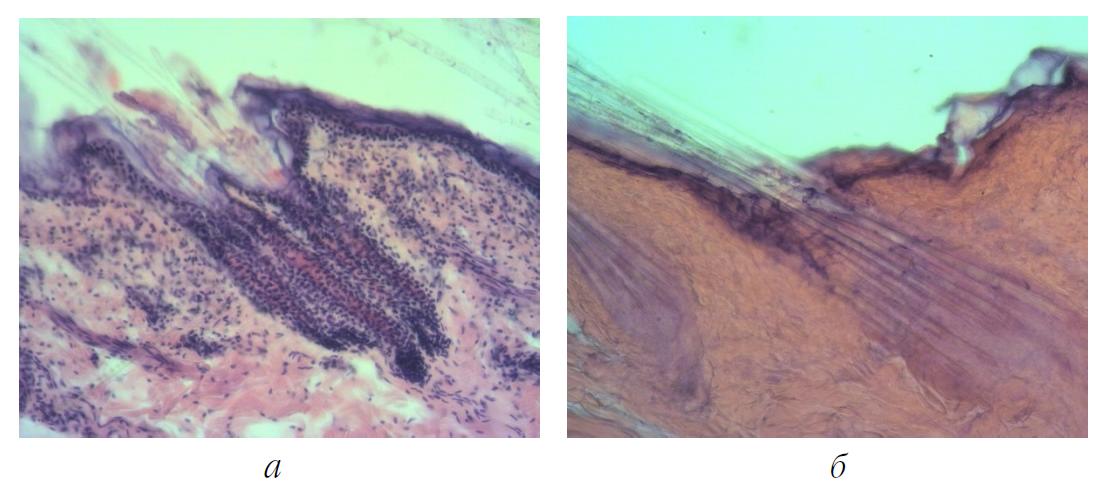

После термостатирования кожных эксплантатов во второй серии с использованием экранов из светонепроницаемой черной бумаги показатели жизнеспособности дермальных тканей оставались высокими и не отличались значимо от результатов опытов первой серии (рис. 3, а).

Рис. 3. Структура кожных эксплантатов: а – во II серии в группе с их экранированием черной бумагой от алюминиевой фольги. Хорошая сохранность ядер клеток эпителиального слоя, слоя собственно дермы и волосяных фолликулов; б – в III серии в группе с их экранированием тонким стеклом от алюминиевой фольги. Некротизирование волосяных фолликулов, эпителиального и собственно дермального слоев. Окраска гематоксилином и эозином, ув. × 100

В третьей серии опытов наметилась тенденция к снижению витальности в группе эксплантатов при их экранировании от кристаллов кремния тонким стеклом. Хотя снижение показателя жизнеспособности эксплантатов оказалось незначимым, лишь в части образцов некротические процессы в их мышечном слое стали несколько более выраженными. Местами поперечная мышечная ткань эксплантатов была некротизирована: определялись только контуры волокон без исчерченности и ядер. Между мышечными волокнами имелись разложившиеся соединительнотканные клетки, в некоторых местах были видны остатки их ядер. Однако в группе эксплантатов, экранированных от алюминиевой фольги тонким стеклом, наблюдалось резкое снижение их витальности, что фактически означало гибель дермальных тканей. Во всех без исключения образцах выявлялись обширные некротические процессы с захватом всех слоев дермы. Определялись только единичные прокрашиваемые пикнотичные ядра на фоне некротизированных волосяных фолликулов (рис. 3, б).